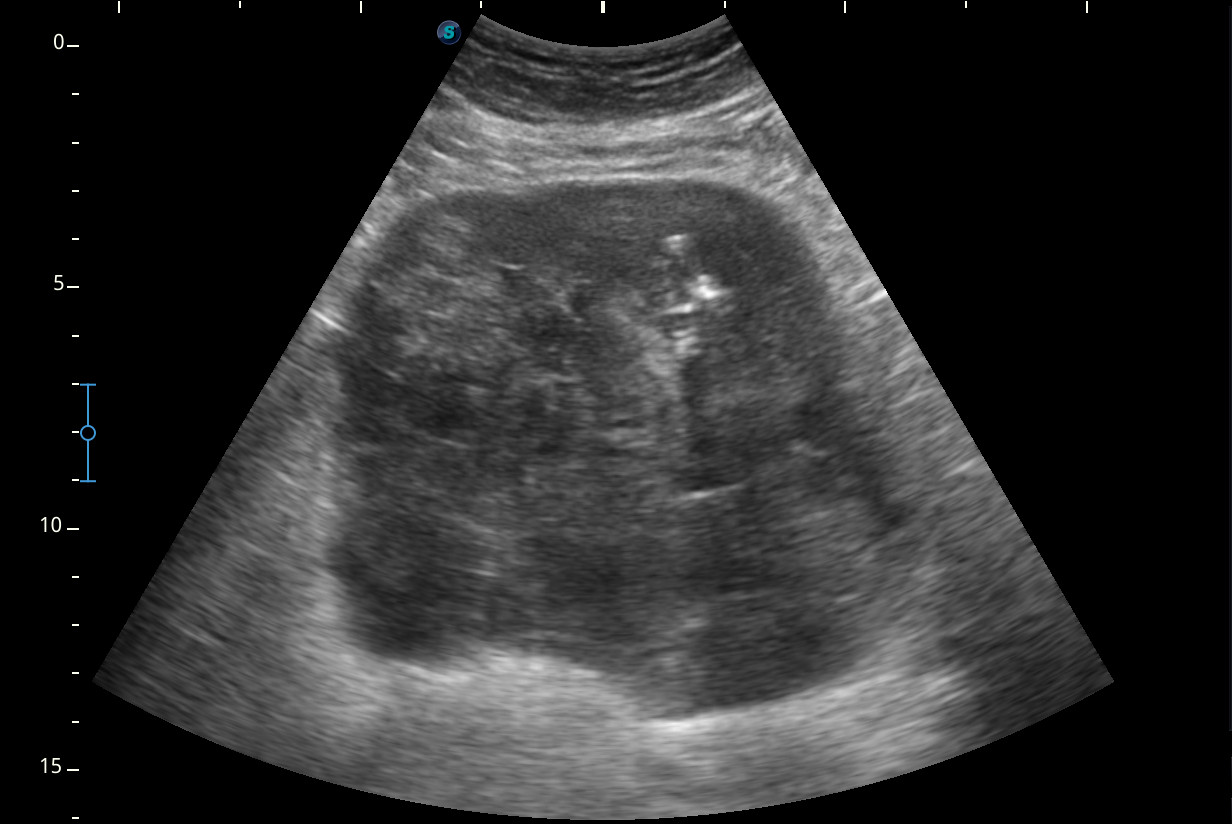

Se visualiza una masa heterogénea de unos 10 x 13 cm aproximadamente de diámetro con posibles focos necróticos y captación Doppler color, de dudosa organodependencia, que podría corresponder a un sarcoma retroperitoneal.